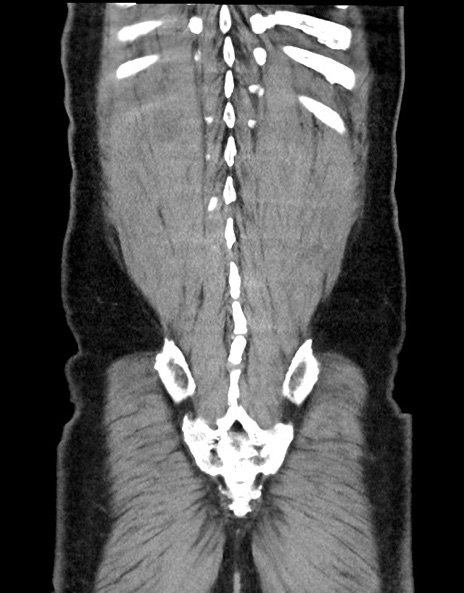

症例15(冠状断像)

【症例】70歳代男性

【主訴】腹痛

【現病歴】今朝から腹痛あり。全体的に痛い。特に左上の方。排ガスが今日はない。冷や汗が出る。

【既往歴】直腸癌術後

【身体所見】左側腹部〜上腹部に圧痛あり。腹膜刺激症状明らかなではない。軽度反跳痛。左下腹部に術後瘢痕あり。

【データ】WBC 7700、CRP 0.02